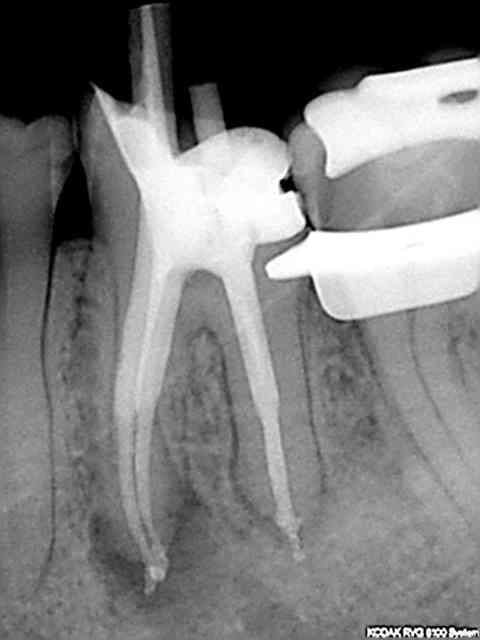

R31 mnpgen - Eugenol

R34 qggho9 - Eugenol